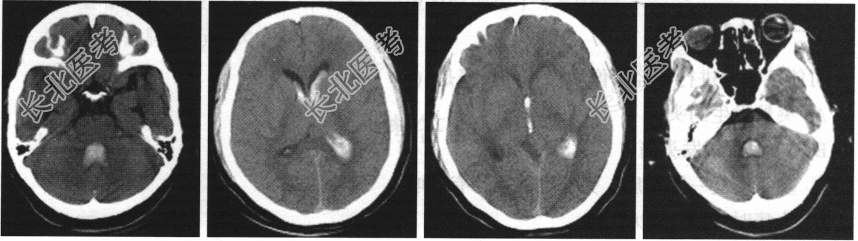

- 单项选择题患者,男性, 43岁。有高血压病史10余年,突发剧烈头痛、呕吐, CT检查如图,该患者最可能诊断为( )

A、脑室内出血

B、外伤性脑出血

C、脑膜瘤破裂出血

D、脑梗死

E、以上都不对